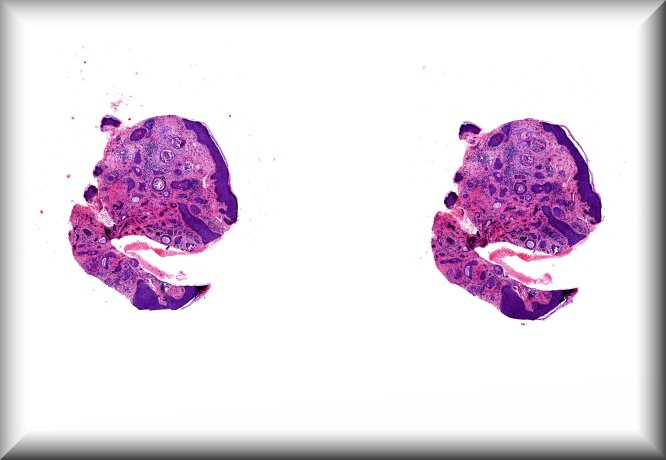

Jolique van Ipenburg (Nijmegen): A thirteen year old girl presents with two conjunctival lesions. The patient reported a traumatic event 2 years earlier, where after she noticed these conjunctival lesions 1 ½ year ago. These lesions seem to become darker over time and people are making remarksfrequently. Clinical examination reveals 2 heavily pigmented mobile highly vascularized lesions located at the bulbar conjunctiva. These lesions do not bleed and are painless. Vision is not impaired. The lesions were excised for both diagnostic and therapeutic reasons. |